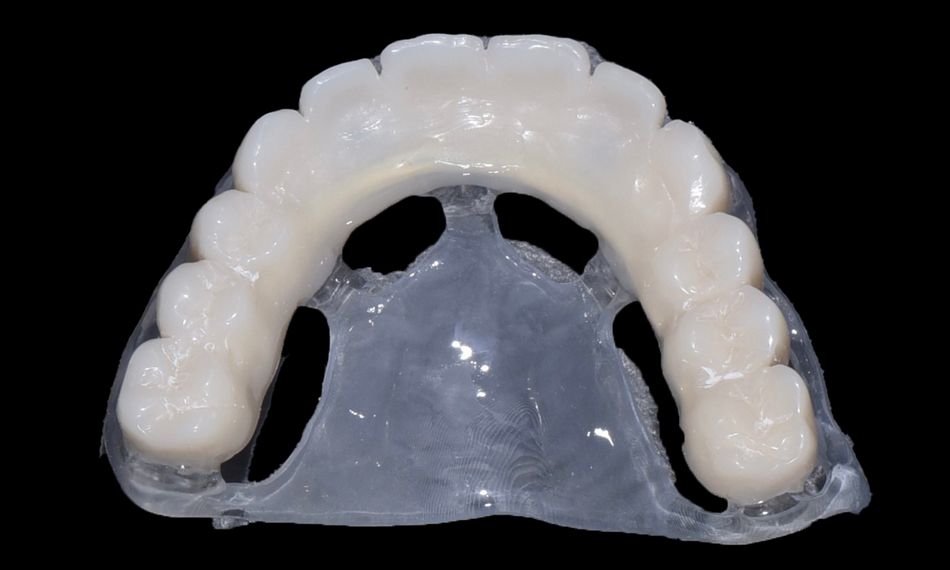

The lab stage involved meticulous attention to detail in manufacturing the full arches. The prosthetic restoration of choice was a maxillary and mandibular metal reinforced acrylic prosthesis. The lab provided the finalized prosthesis including the LOCATOR FIXED® Housings with pre-assembled black processing inserts to the dental practice.

The next step involved placing the LOCATOR FIXED® Inserts into the housings. The selection of LOCATOR FIXED® Inserts was tailored to the specific indication. In cases involving five or more implants per arch, tan and blue shaded inserts are utilized. This procedure achieved by aligning the insert with the housing and applying firm downward pressure with the LOCATOR® Systems Core Tool until the insert snapped securely into place (Figs. 23-28).